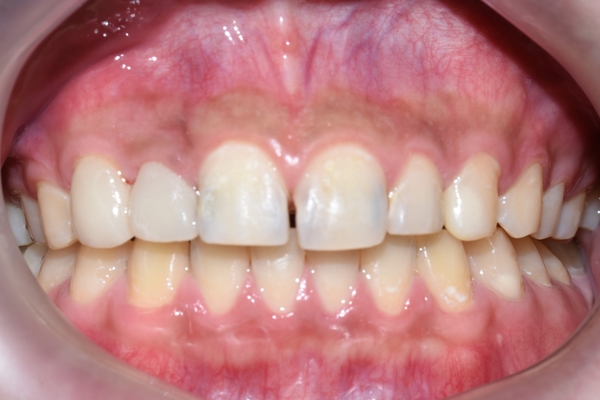

그래도 굉장히 심한 충치 치아의 치료 후에 환자분은 눈으로 결과가 보이다 보니 만족하셨습니다! 거의 치아성형수준이죠!

실제 치료기간: 앞니 신경치료 일주일이내, 라미네이트, 인레이 등 보철물 제작 4~5일, 레진치료 당일완료